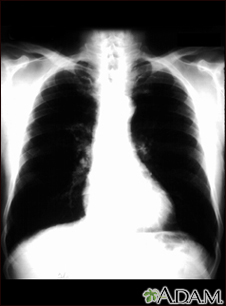

Bronchial cancer - chest x-ray